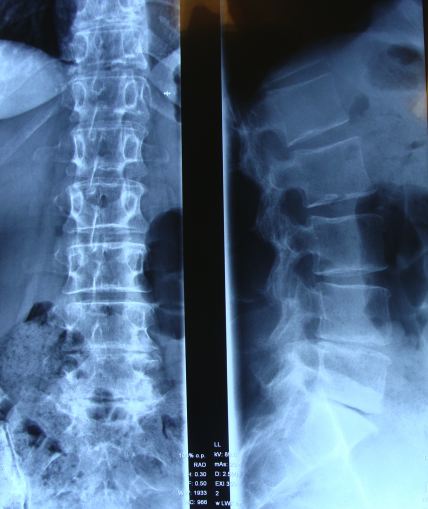

Almost invariably when then there is a radical discectomy at one level, it's nearest neighbour crumbles too. Notice the air in the joint (it looks black), the so-called vacuum phenomenon associated with a collapsed joint. Is there a back surgery alternative today?

This is the Xray of a 63 year old woman. It was taken lying down so you can't detect the short leg. Thirty years ago, she told me, she didn't have back surgery alternatives when she had a slipped disc with severe lower back and leg pain. The details obviously after all this time are a bit sketchy, but she recalls being stuck in an antalgic position for two months. She hadn't heard of chiropractic, and no one suggested it.

She underwent a radical discectomy at the level L5 S1 in the Netherlands; there were in any case very few chiropractors at that time. The surgery was reasonably successful; the pain in her leg was relieved within a few days, and she could stand up straight, but the pain in her back, mild it's true, never went away. Sitting has remained a problem ever since the operation.

Progressively over the years the stiffness in her back increased; now we can see why, because the L4 L5 joint was disintegrating; the level above the surgery. Three years ago it started to become unbearable with pain radiating on and off down the side of her leg from the L4 L5 level. Sitting for any length of time became intolerable.

On examination, a short left leg was immediately obvious; she wore a heel lift prescribed by a podiatrist which enabled her to walk without pain, otherwise ambling and standing were difficult. Ranges of motion were remarkably good, and tests for an injured or irritated nerve were negative.

Motion revealed fixations in the left sacroiliac joint and at L4 and L5.

Lateral bending provoked pain in the back, and some sacroiliac joint tests were positive.

The overall conclusion was mechanical lower lumbar and sacroiliac joint pain with no significant nerve root involvement.